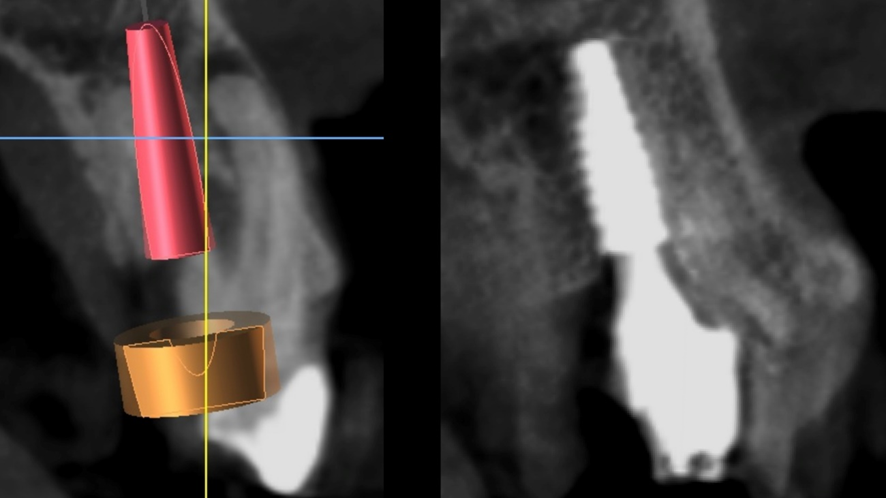

O planejamento reverso, bem como a correta solicitação dos exames complementares e a interpretação correta desses exames vem se demonstrando um aliado importante para realizar implante imediato com carga imediata. Dentre os exames complementares temos a tomografia computadorizada Cone Beam, a qual proporciona uma visão tridimensional das estruturas ósseas, possibilitando visualizar a espessura óssea, grau de densidade óssea e relação com estruturas anatômicas nobres, favorecendo a escolha dos melhores sítios de instalação dos implantes.7,9

Com o correto planejamento digital através da tomográfica computadorizada e um escaneamento digital da região, a técnica da cirurgia guiada surge com um procedimento previsível (DAL PIVA et al., 2018). O guia cirúrgico propriamente dito é obtido a partir do planejamento virtual, onde já foi definido pelo implantodontista o número de implantes e onde eles serão instalados, transferindo o planejamento virtual para o real através da guia impressa.7,11

Para o planejamento reverso foi realizado escaneamento digital e obtido o modelo digital da boca do paciente, assim como também a tomografia Cone Beam da regão para a confecção do guia cirúrgico. Foi planejando também a necessidade de realizar enxerto ósseo do tipo heterogêneo com colágeno para o preenchimento do GAP da região, visando assim criar um bom perfil de emergência e reduzir a chance de perda volumétrica. Foi planejado também um provisório de PMMA a partir de software de planejamento e enceramento digital 3D (Exocad).

Após a exodontia foi posicionado o guia cirúrgico impresso e iniciou-se o protocolo de fresagem do kit cirúrgico Implaguide da Implacil De Bortoli: fresa lança 2,0, seguida pela fresa 3,5×13, buscando subfresagem para maior estabilidade primária. O implante dentário instalado foi o Maestro de 4x13mm (Implacil De Bortoli). Foi realizado em seguida a instalação do pilar Ideale 4,5 x 4 x 2,5 mm e a coifa parafusada do pilar Ideale 4,5x4mm.